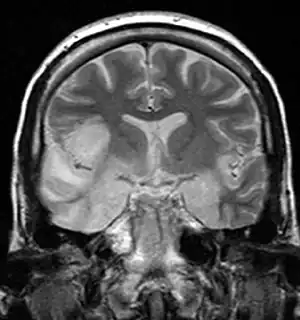

| MRI scan image shows high signal in the temporal lobes and right inferior frontal gyrus in someone with HSV encephalitis. | |